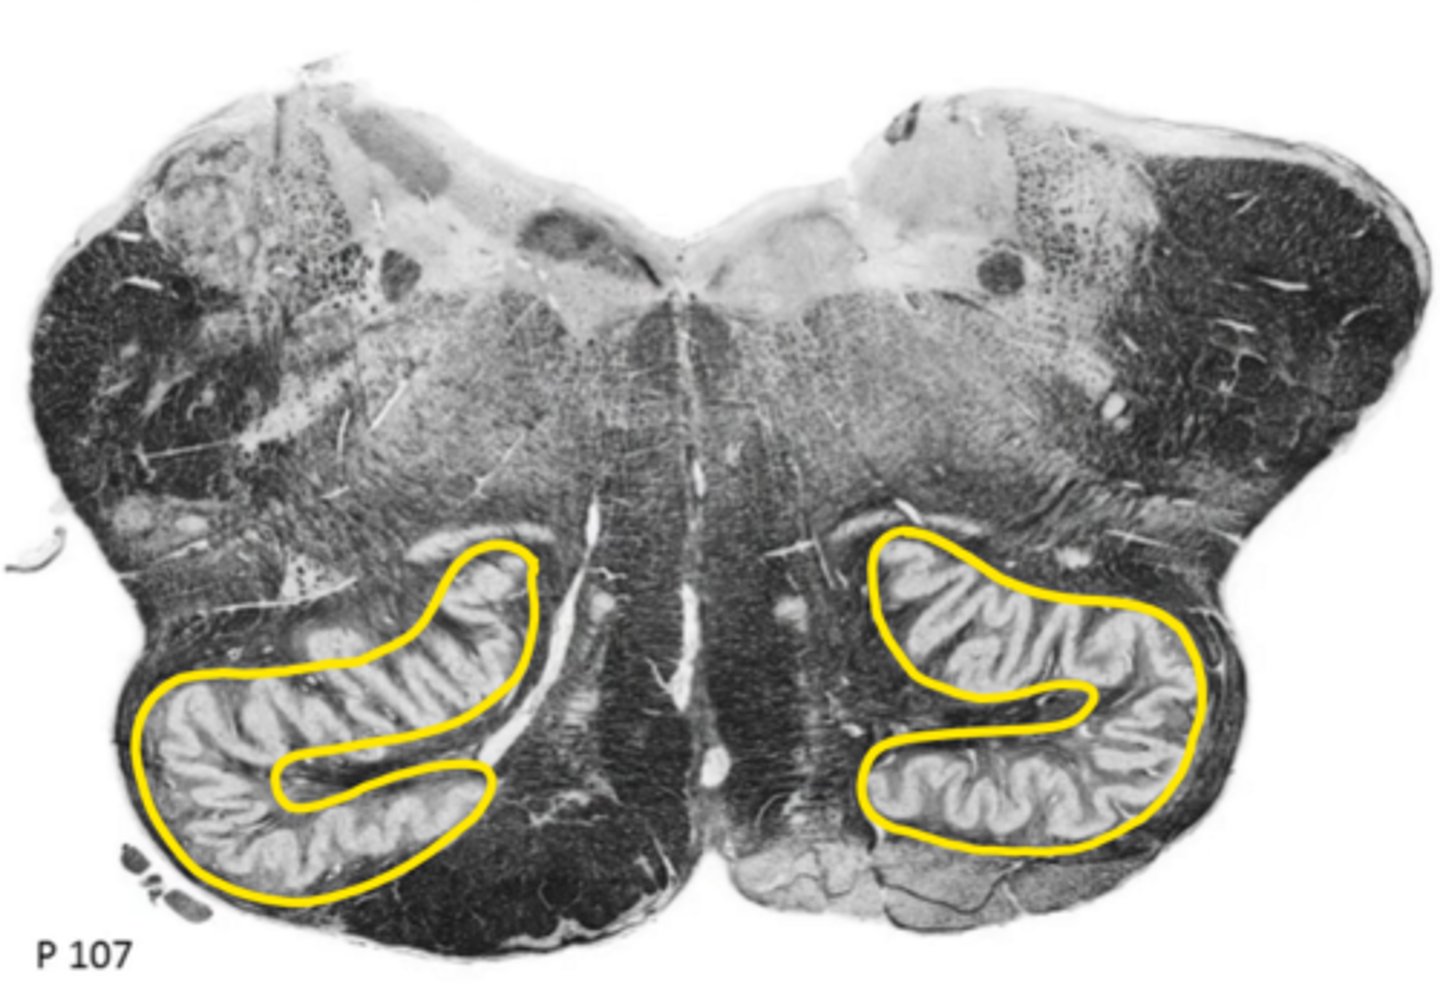

open medulla

ID the brainstem level